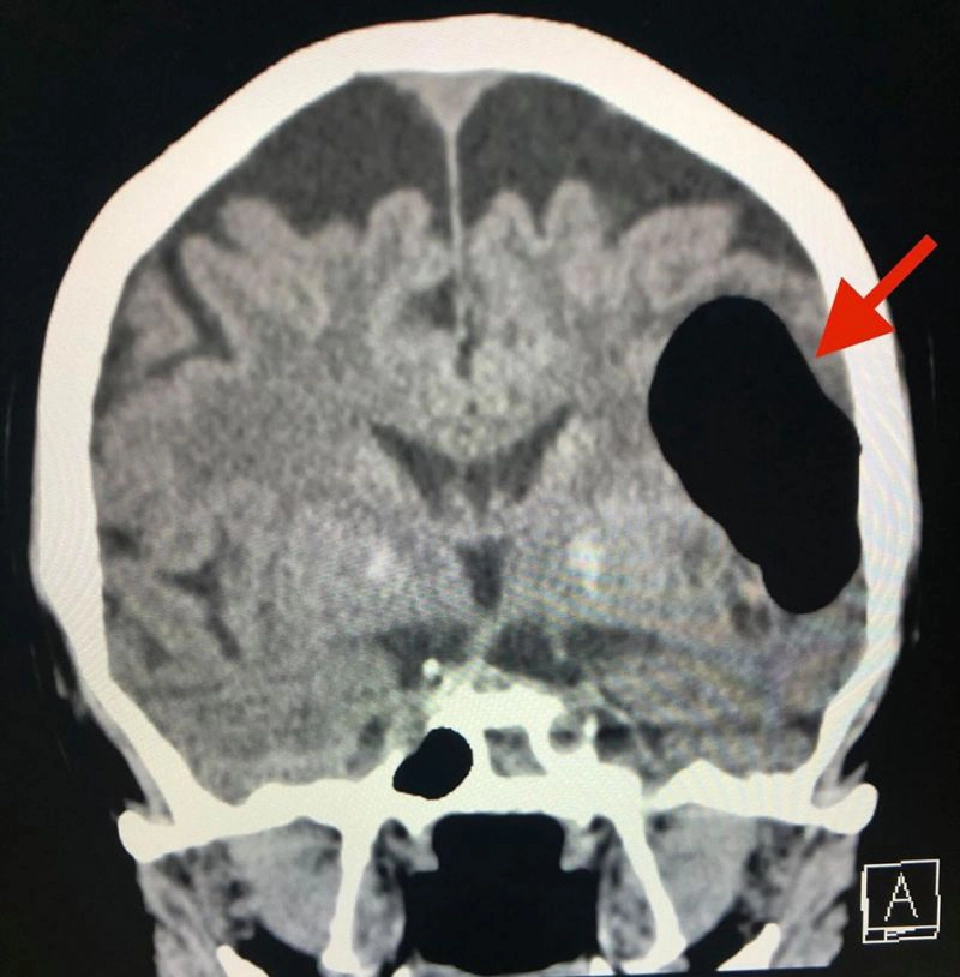

วันที่ 14 พฤษภาคม 2563 ผู้ป่วยกลับมารพ.อีกครั้งหลังจากจามแล้วเอามือปิดปากปิดจมูกเพราะไม่อยากให้มีเสียงดัง หลังทำมีอาการพูดไม่ชัด หน้าข้างขวาเบี้ยว หูข้างซ้ายอื้อ มีเสียงดัง ทำคอมพิวเตอร์สมองพบลม (air pocket) ในเนื้อสมองข้างซ้ายขนาด 5.1 × 4.1 × 2.8 เซนติเมตร (ดูรูป) ตำแหน่งเดิมเหมือนเมื่อ 3 ปี 5 เดือนก่อน แต่ปริมาตรของลมในเนื้อสมองครั้งนี้น้อยกว่า ผู้ป่วยนอนในโรงพยาบาล 4 วัน อาการดีขึ้นช้าๆ กลับบ้านได้